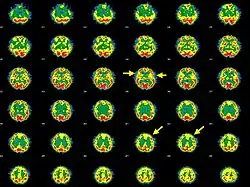

Brain SPECT transaxial images of a patient afflicted with Hashimoto's encephalopathy showing cerebral hypoperfusion in the left frontal lobe and in both temporal lobes (arrows).